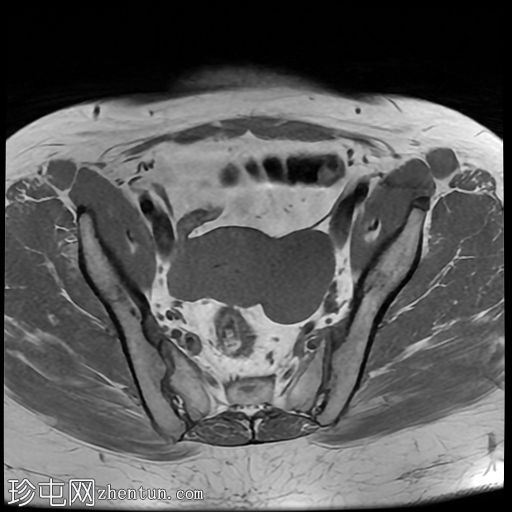

轴位

T2加权像

左侧卵巢增大,呈弥漫性低T1信号和高T2信号,可见周边卵泡,部分卵泡除周边卵泡周围有环状强化外,无明显实质强化。左侧附件蒂呈漩涡状,提示卵巢扭转。